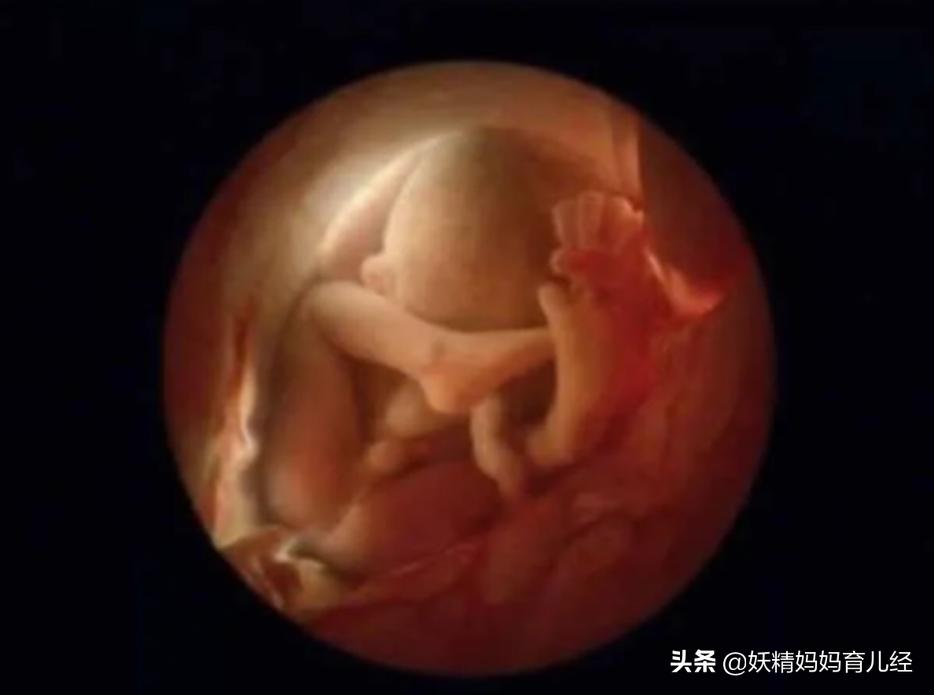

我想有这种*窥偷**欲望的孕妇,肯定不止我一个。于是,我就找遍很多网站和论坛,终于发现了这些照片。这些照片是瑞典摄影师Lennart Nilsson历时12年的时间,利用显微镜和内窥镜记录下生命孕育的神奇旅程。

这些照片1956年最早发布美国的《life》杂志上,让人们感受到生命神奇的同时,也感受到孕育的美丽。

16、怀孕24周,胎儿胎动非常活跃,不是游泳,就是翻跟头。妈妈注意了,胎动也是宝宝健康的重要标志。建议孕妇要学会数胎动,如果有异常胎动,就是宝宝在求救。